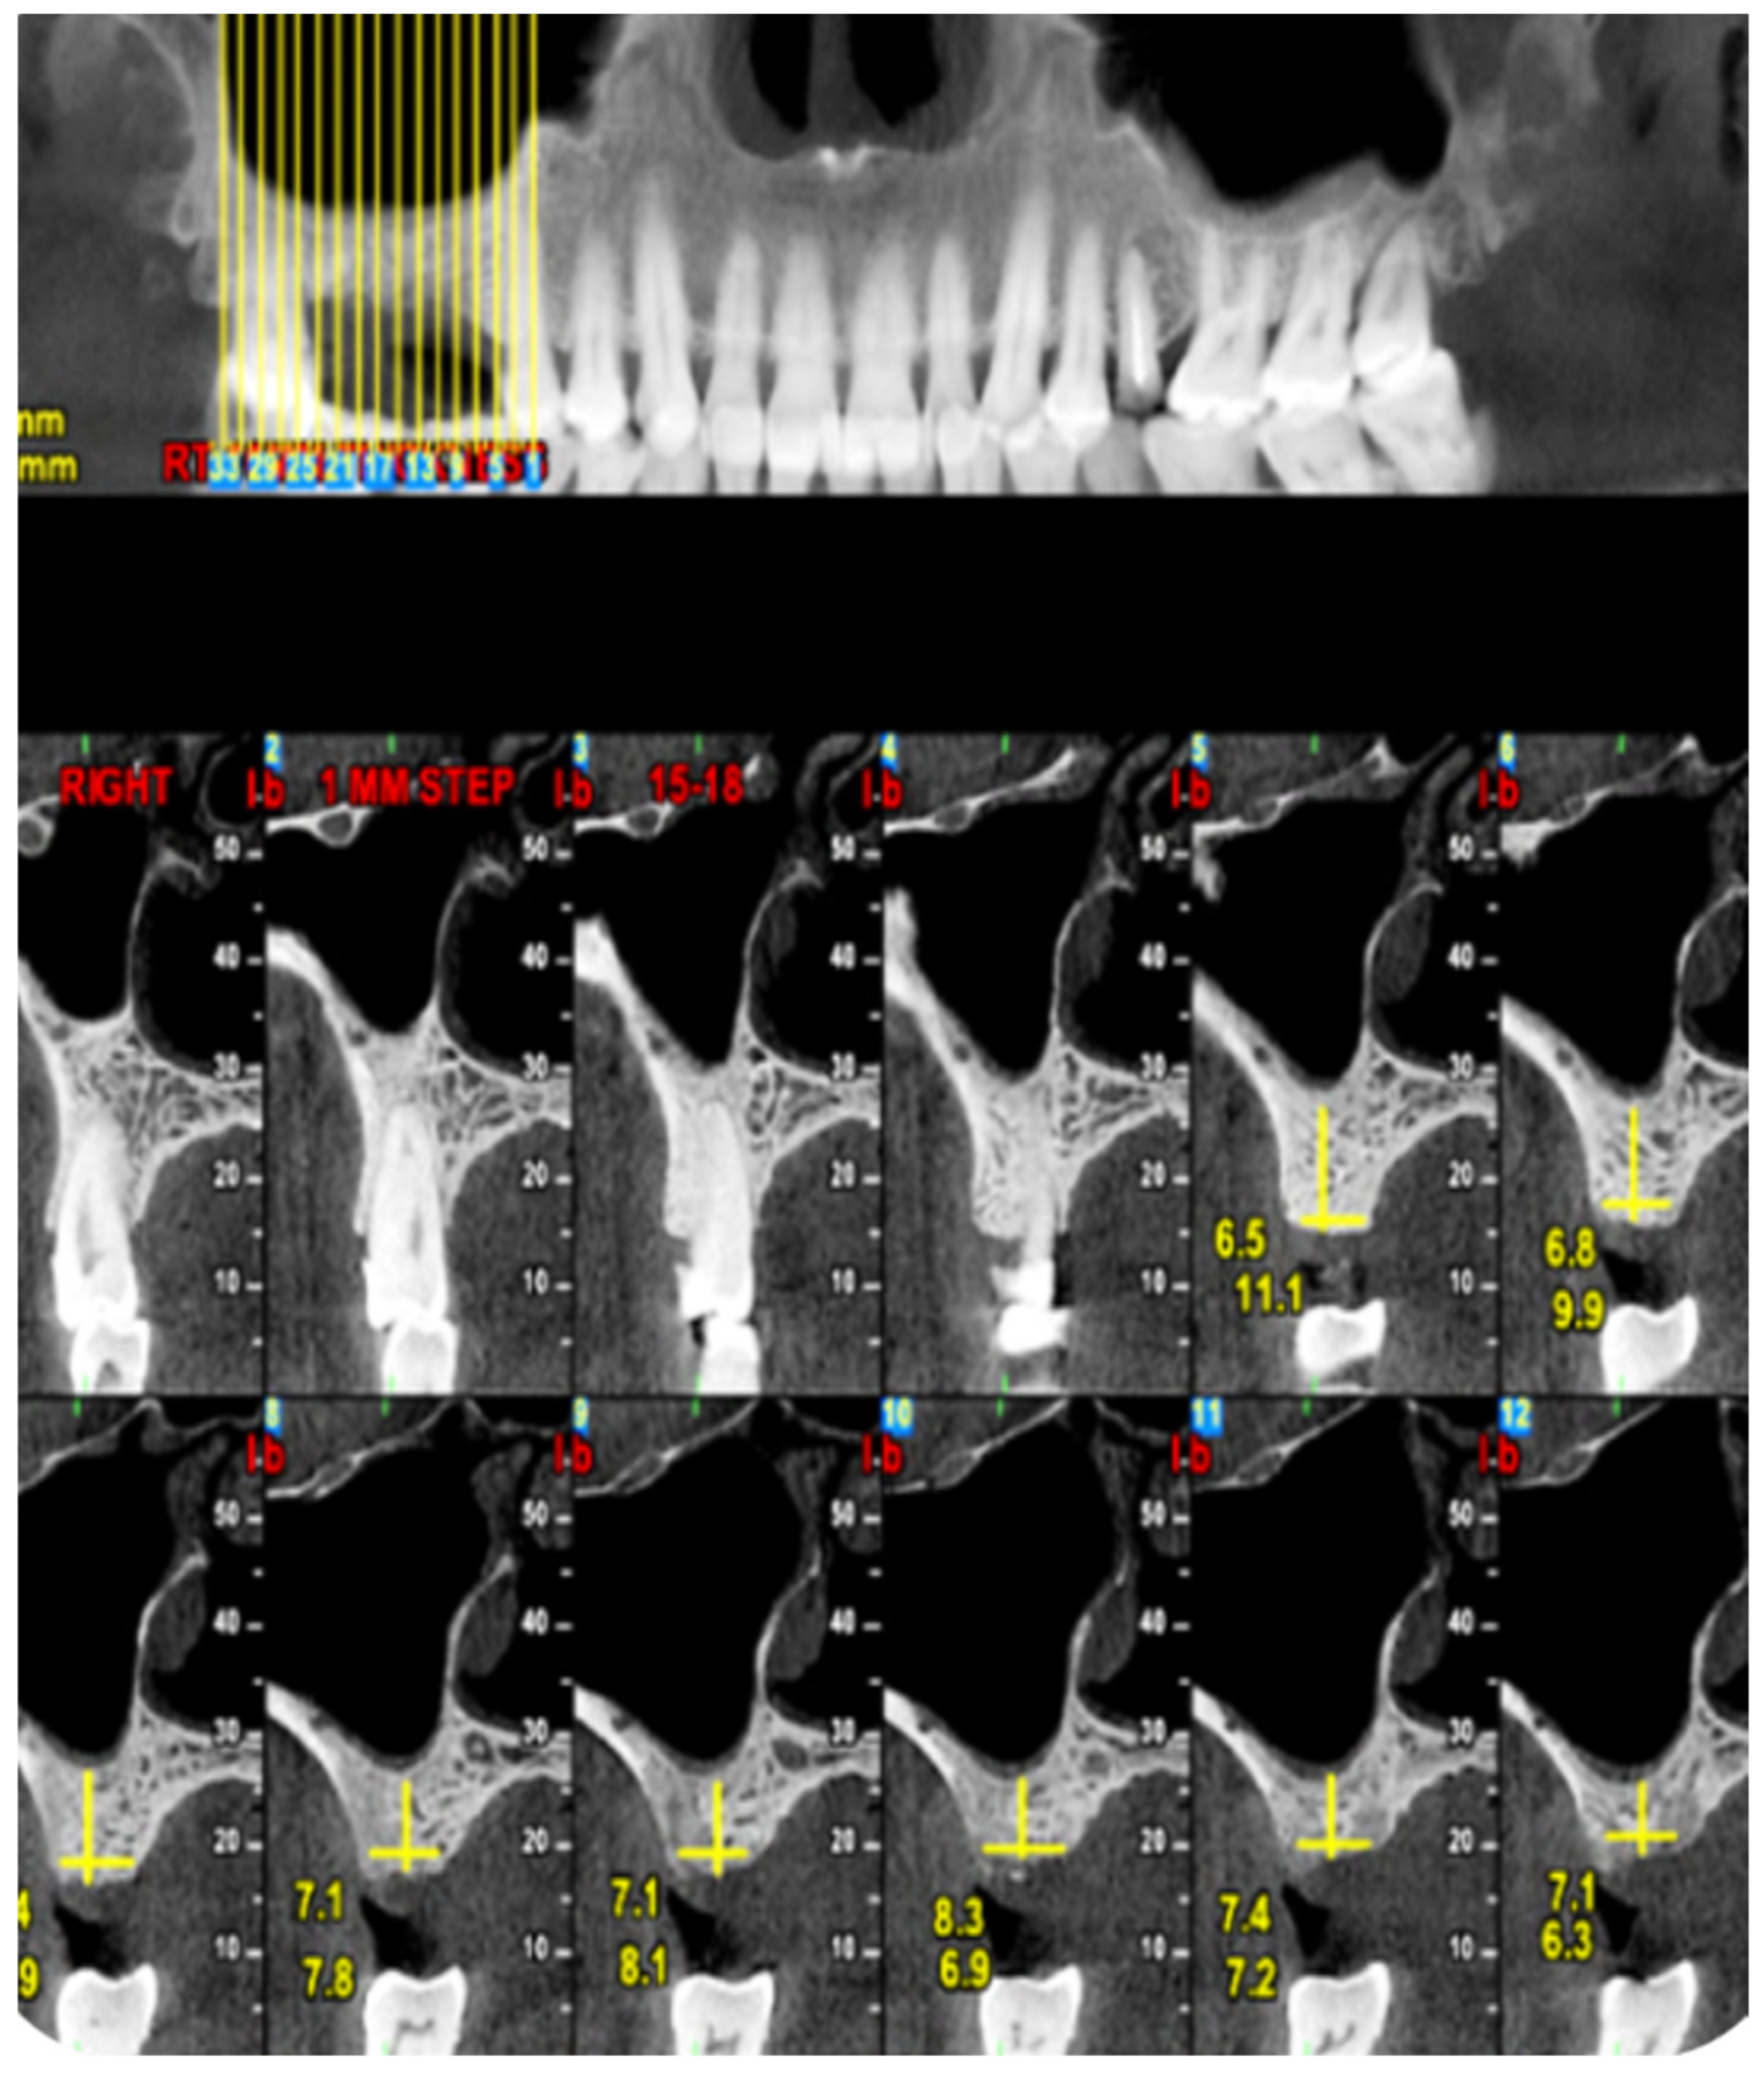

2. Materials and Methods

2.1. Standard Surgical Procedure